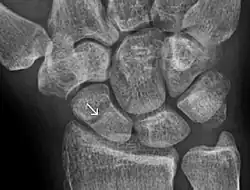

- ↑ Jarraya, Mohamed; Hayashi, Daichi; Roemer, Frank W.; Crema, Michel D.; Diaz, Luis; Conlin, Jane; Marra, Monica D.; Jomaah, Nabil; Guermazi, Ali (2013). "Radiographically Occult and Subtle Fractures: A Pictorial Review". Radiology Research and Practice. 2013: 1–10. doi:10.1155/2013/370169. PMC 3613077. PMID 23577253.